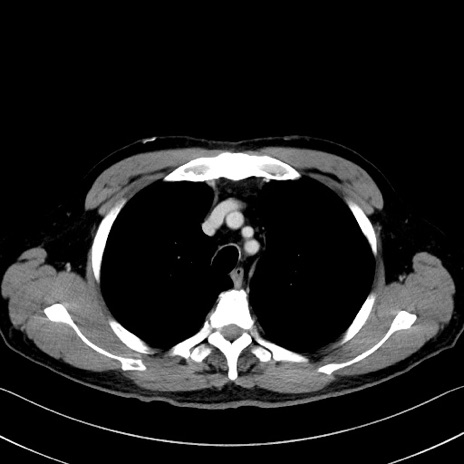

症例35(横断像)

【症例】70歳代 男性

【主訴】腹部膨満、嘔吐

【現病歴】昨日より腹部膨満感出現。本日増悪し、仙痛出現。嘔吐あり、受診。

【既往歴】糖尿病、胆摘後

【身体所見】BP 149/80mmHg、HR 74/min、BT 35.9℃、腹部:膨満、軟、圧痛なし。腸雑音減弱あり。上腹部正中切開瘢痕あり。

【データ】WBC 13500、CRP 1.72